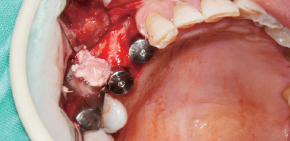

使用Ø3.5/4.0 Harvesting Drill的临床案例。

by Dr. Soohong Kim, DDS, Ph.D

确认种植体和采集部位后,一边注水一边以300rpm的速度钻孔。

根据不同的骨高度贴紧Silicone Shield,防止骨片遗失。

通过透明的Silicone Shield轻松地确认骨采集量。

在钻头上分离Silicone Shield和塞子后,将采集好的骨片放到Bone Dish中。

植入种植体后连接愈合基台,在缺损部位进行GBR。

*采集的第二部:钻孔4mm后,若塞子和Silicone Shield中装满了骨片,则将采集好的骨片放到Bone Dish后更换为7mm钻。